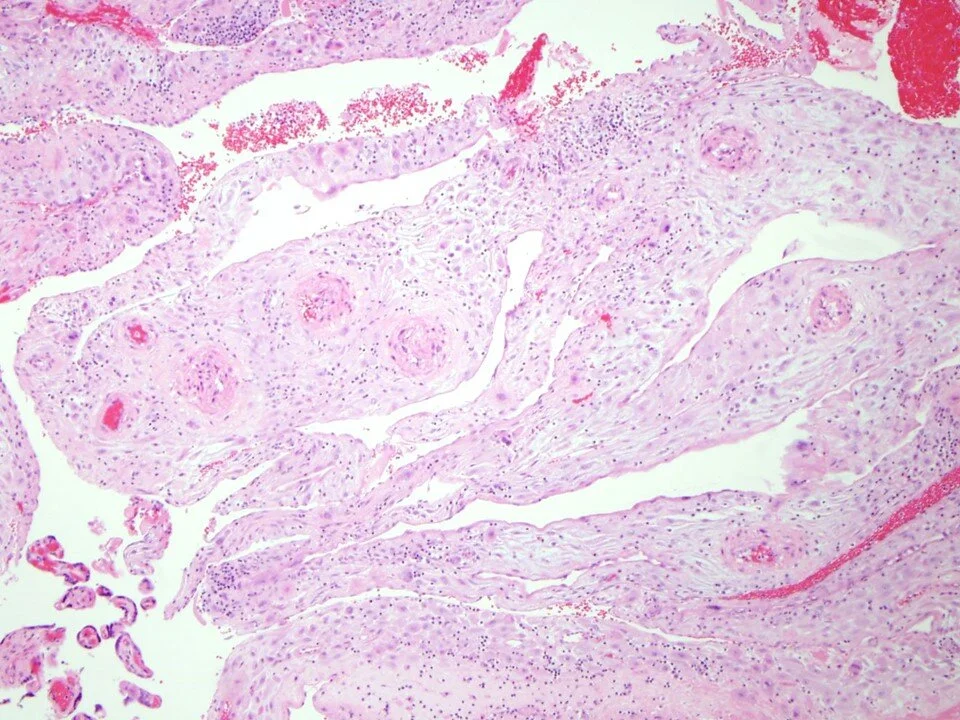

Acute chorioamnionitis: neutrophils extend into fibrous chorion

Chorionic vasculitis - inflammation involves chorionic plate vessels